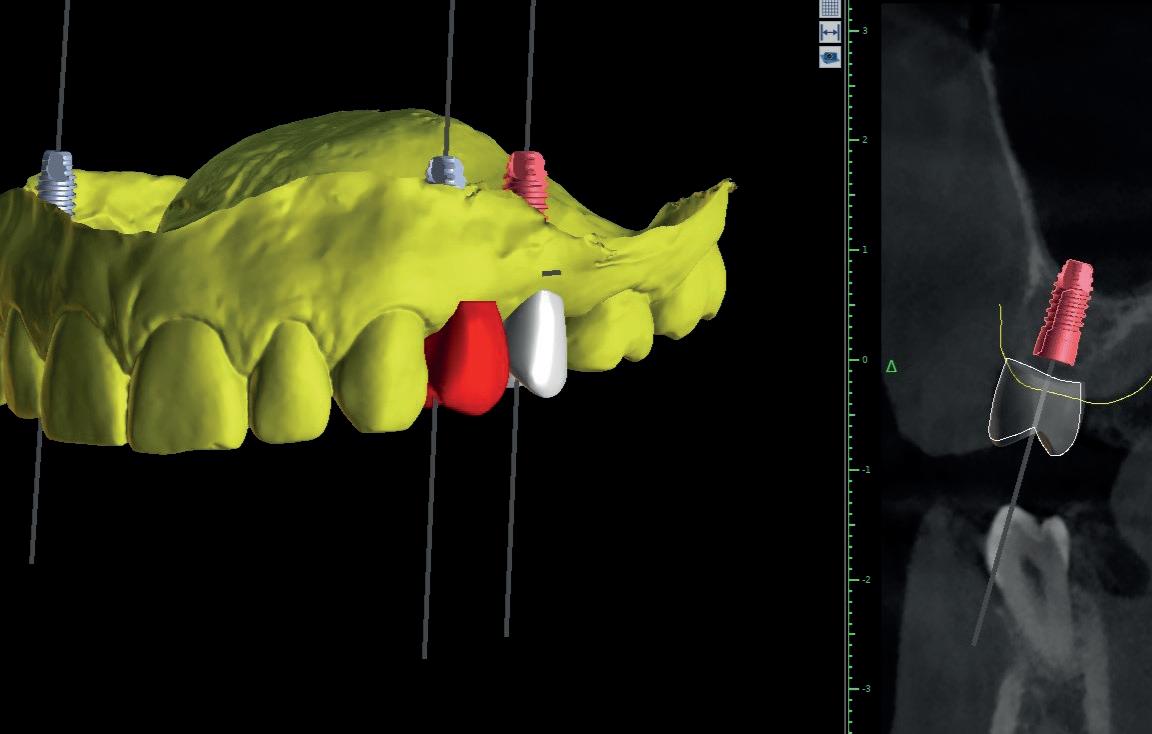

Ook op het gebied van software ontwikkelt het vak zich enorm. Zeker met de komst van AI (Artificial Intelligence) Gijs: “Wij implementeren op dit moment nieuwe software (DTX Studio Clinic). Hierin worden alle data gecombineerd en gelinkt zoals bijvoorbeeld solo röntgenfoto’s, panoramische opnames, CBCT-beelden, klinische licht foto’s en STLfiles vanuit de intra-orale scan. Deze worden in de software herkend en door de software in DTX naar de juiste elementen herleid. Daarbij worden door de software ook anatomische structuren zoals bijvoorbeeld de nervus mandibularis herkend en ingekleurd.

Door middel van AI in DTX Studio worden focusgebieden gemarkeerd op intraorale röntgenbeelden voor tandheelkundige bevindingen, zoals cariës, apicale laesie, wortelkanaaldefect, marginaal defect, botverlies en calculus (tandsteen). Uiteraard dient dit focusgebied door de behandelaar te worden gecontroleerd om tot een diagnose te komen. Het voorstel van de software zal dan worden gevalideerd dan wel worden afgewezen door de behandelaar. Ook wordt er steeds meer gebruik gemaakt van Guided Surgery en bij het vervaardigen van de proefopstelling en de implantaat planning speelt AI een steeds belangrijkere rol. Daar waar voorheen het laboratorium te extraheren elementen moest raderen en een set-up vervaardigen, kan dit inmiddels ook in de planningssoftware. Met deze planning kan guided met een boormal of door middel van navigatie worden geïmplanteerd, maar ook als er freehand wordt gewerkt, wordt er meestal vooraf een 3D-planning vervaardigd.”

Na vier maanden wordt er een CBCT gemaakt om het botvolume te kunnen beoordelen en een digitale planning te kunnen maken voor het plaatsen van het implantaat. Tevens wordt de stabiliteit van de botpieken op het buurelementen bekeken (foto 15 en 16).